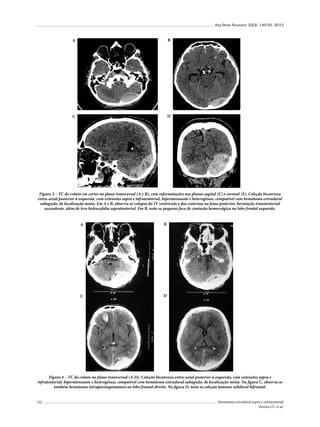

total, 59,3% apresentaram uma fratura de crânio antes

do primeiro ano de vida, sendo o intervalo entre o TCE

e o diagnóstico da FEC de um dia a oito anos.

Nossa revisão da literatura feita num total de 127 casos19,25-29 mostrou que as quedas (74,8%) são a principal

causa de FEC, seguidas de acidentes automobilísticos

(20,5%), iatrogenia (3,1%) e maltrato infantil (1,6%).

Em nosso estudo, foram internadas 19.758 crianças

com TCE em um período de sete anos; 6,3% dos internamentos apresentaram fratura craniana, dos quais cinco